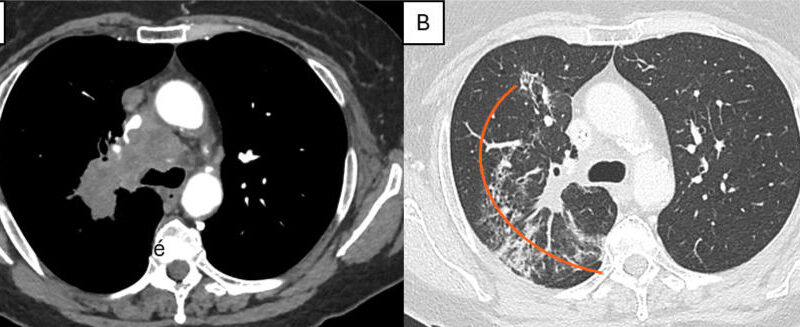

Et si l'intelligence artificielle (IA) permettait de détecter la fatigue chez le radiologue avant même qu'il s'en aperçoive ? Pour en avoir le cœur net, Bulat Ibragimov, professeur au sein du département de sciences informatiques de l'université de Copenhague (Danemark), et ses collègues, ont analysé la proportion des poumons observée par quatre radiologues sur une station de travail munie de suivi oculaire. D’après leurs résultats, publiés le 9 janvier dans Journal of Digital Imaging, le champ de vision des radiologues diminue de 1,3 % à 7,6 % toutes les 100 radiographies thoraciques, quelles que soient les anomalies présentes sur les images [1]. Cette baisse de la couverture visuelle des images, expliquent-ils, pourrait informer les radiologues qu’il est temps de recourir à une validation extérieure.

Pour analyser les mouvements oculaires des radiologues, les auteurs de l'étude en ont recruté quatre, auxquels ils ont demandé d’interpréter 400